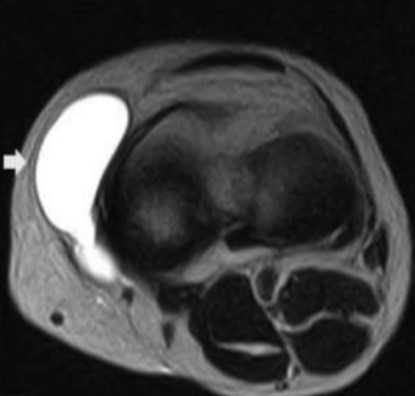

Препателлярный бурсит

Воспаление передней подкожной преднадколенниковой сумки на МРТ (стрелка)

Препателлярная бурса представляет собой трехкомпонентную структуру. Поверхностный отсек находится между подкожной клетчаткой и продолжением широкой фасции бедра, средний - между поперечной поверхностной и промежуточной косой фасциями. Глубокий ограничен косой соединительнотканной оболочкой и продольными волокнами сухожилия прямой мышцы бедра. Воспаление указанной синовиальной сумки происходит от длительного стояния на коленях, патологию регистрируют при подагре. Основные клинические проявления - боль и припухлость. Хроническая травматизация приводит к воспалению и геморрагическому бурситу. На МРТ препателлярный бурсит проявляется в виде овального жидкостного образования между подкожной клетчаткой и надколенником.